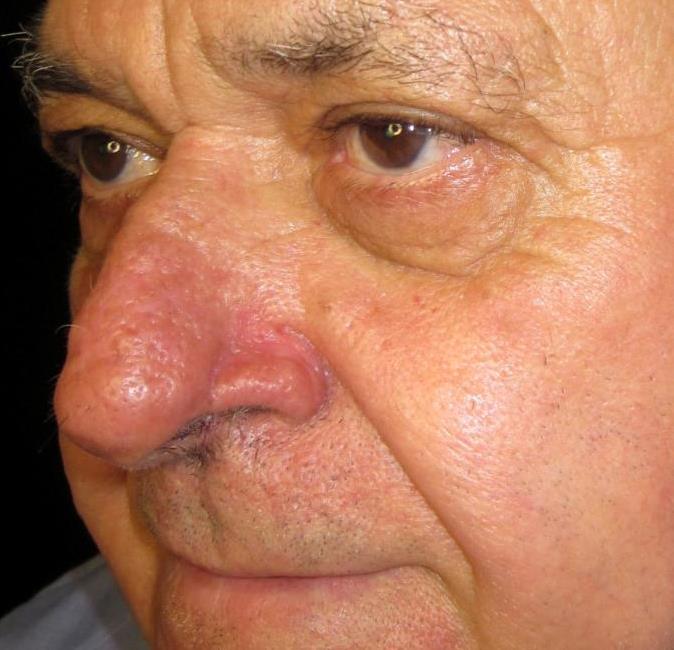

Trước

Hình ảnh minh họa

Sau

Hình ảnh minh họa